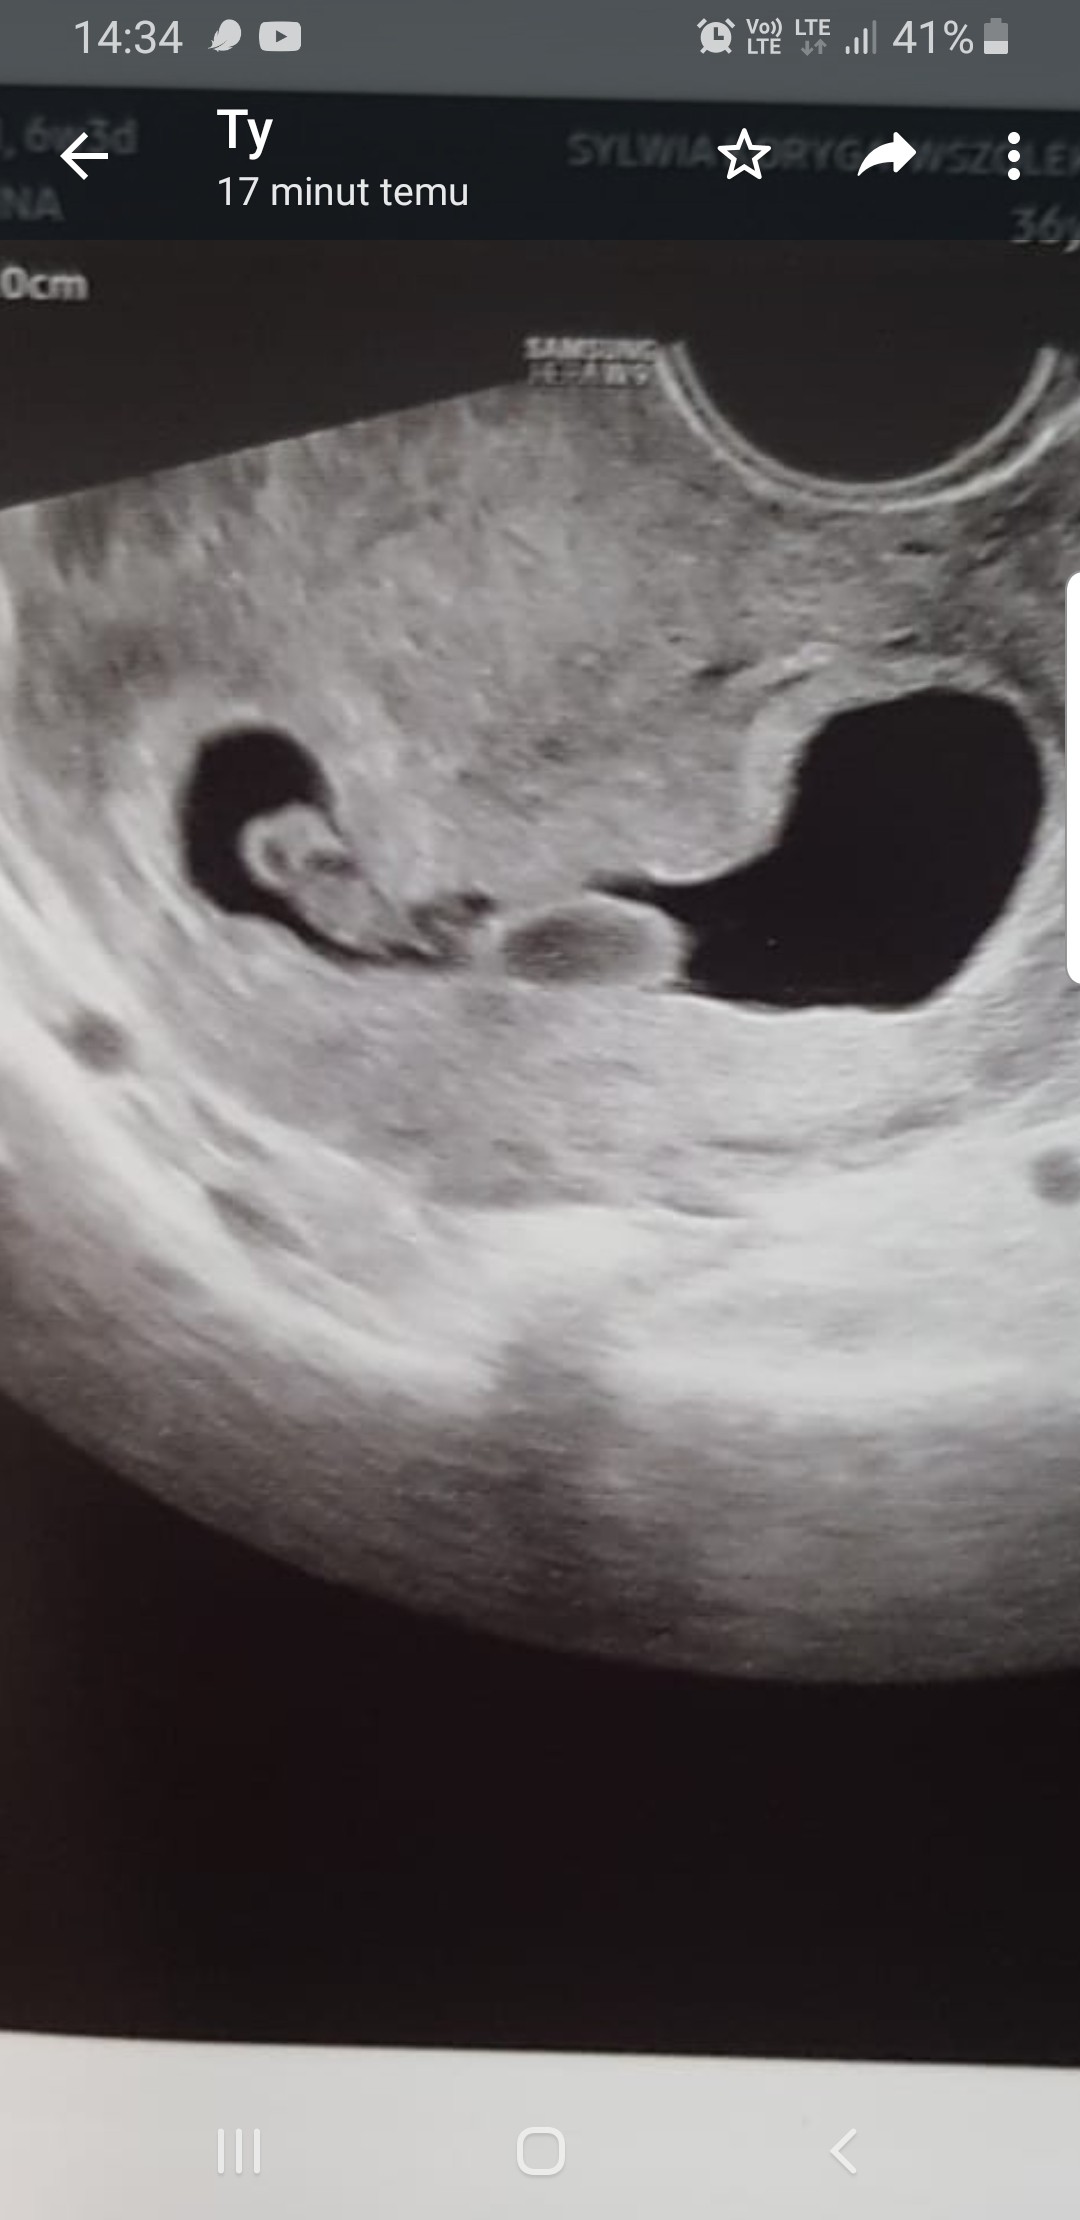

Cześć. Witam się. Lekarz powiedział że najpewniej są bliźniaki choć nie był w stanie inaczej obrócić, i tak na 100% nie wiadomo... w pon byłam na wizycie było 7+1, tydzień wcześniej byłam na NFZ i pikały 2 rzeczy ale to była jedna wielka plama i lekarz sam nie umiał mi powiedzieć o co chodzi... W rodzinie żadnych bliźniąt nie było. Na pokładzie 2ka starszakow, 2 ciążę stracone w ciągu ostatniego roku a tu takie coś... Co myślicie jako doświadczone? Na moje oko są 2 jednojajowe... po prawej dali się zmierzyć, serduszko bije, wszystko ok. Po lewej został i nazwane "dziwną strukturą do obserwacji".

No to u Ciebie 2jajowa to od razu widać 2 pęcherzyki w macicy. U mnie to wygląda na jednojajową i już się martwię.

Na spokojnie, nie ma co się martwić na zapas. Mogą być też dwujajowe ale jakoś ściśnięte. Jak dla mnie to nie wygląda na jedną owodnię. Kiedy teraz masz USG?